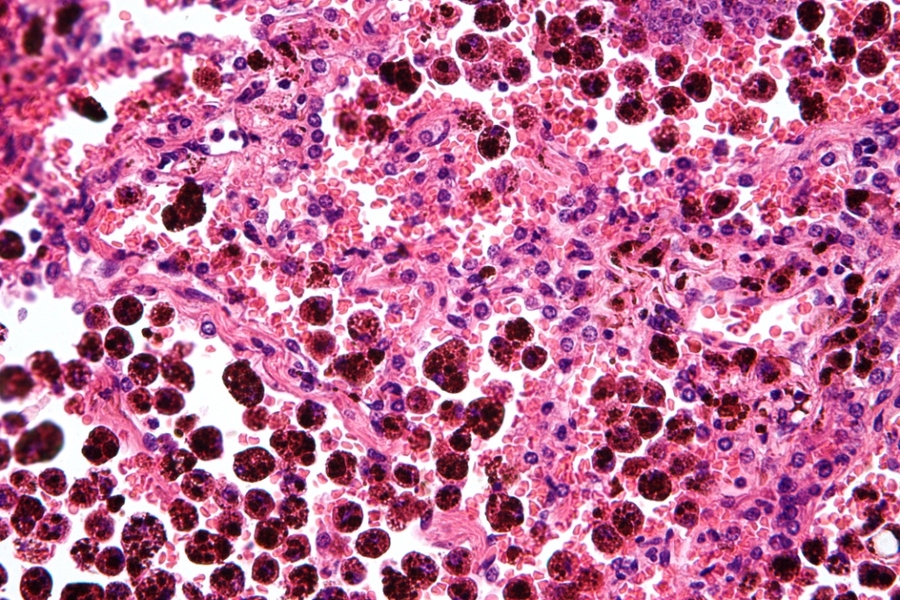

史丹佛大學的史考特麥克萊倫博士發現,「以毒攻毒」可有效抑制這種情況。麥克萊倫表示,某天在研究工作開始前發現,小老鼠的白血病細胞被活化後,癌細胞便隨之減少、病原體也被殺死。研究人員進一步分析發現,原來是停滯生長的祖細胞(癌細胞)受刺激後,轉化為可以保衛人體的巨噬細胞。

巨噬細胞的任務,除了吞食細胞殘骸外,也會攻擊病原體及癌細胞。研究人員拉維瑪嘉提表示,因為B細胞急性淋巴性白血病讓體內的細胞型態,停滯在祖細胞階段,在透過不同的轉錄因子刺激、被這些細胞的蛋白質吸取後,細胞的DNA序列便會被活化。麥克萊倫指出,被這種方式強迫「長大」的癌細胞們,反而成為抗癌的最佳助手。

研究人員發現,這種方式成長的巨噬細胞不僅能減少病原體,還會呼叫免疫系統中的防衛者共同打擊癌細胞。瑪嘉提說,因為這些巨噬細胞是由癌細胞所轉化而成,因此可以透過自身帶有的癌細胞化學訊號,輕鬆的分辨出人體內的有害細胞,使癌細胞們無處可躲,讓抗癌變得更加容易。